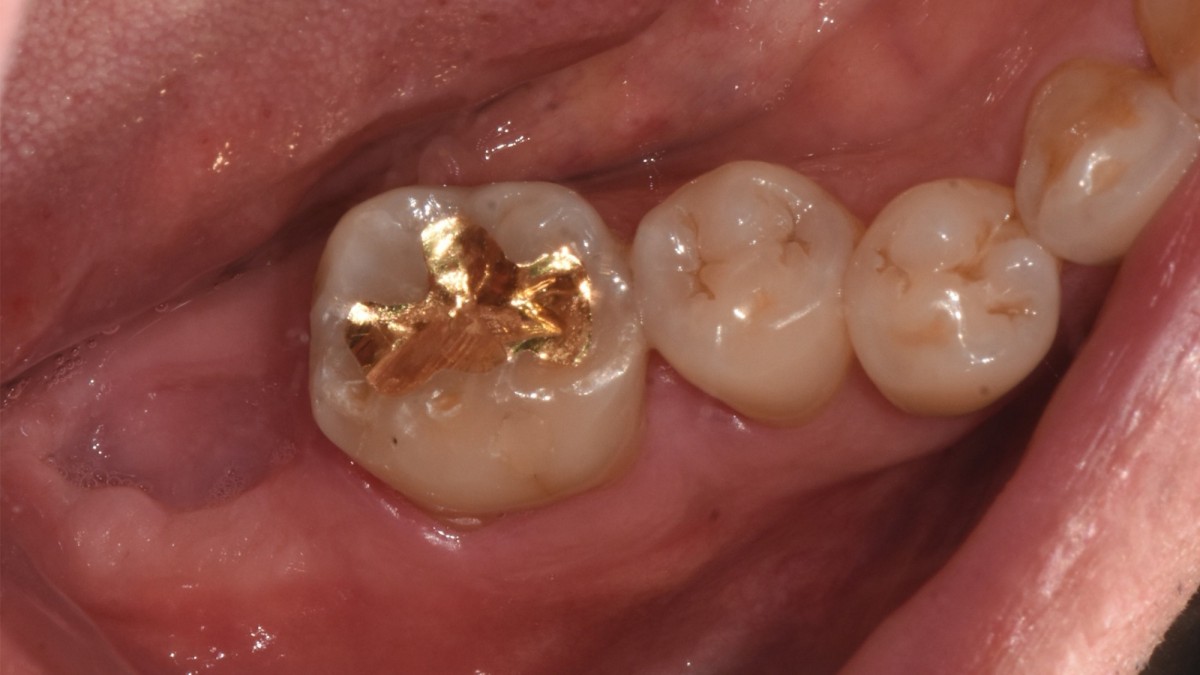

▲torque value after insertion

▲Arum Dentistry NB1 5*10